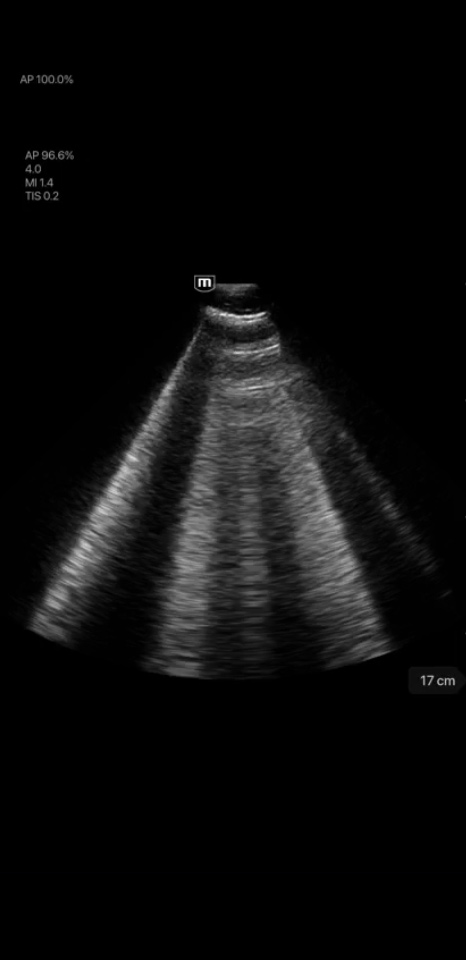

Clinical Images

Mitral and Tricuspid Regurgitation

Pericardial Effusion

Ascites

Dilated Cardiomyopathy

Tissue Velocity Doppler

Lung B-line

Clinical Images

Mitral and Tricuspid Regurgitation

Pericardial Effusion

Ascites

Dilated Cardiomyopathy

Tissue Velocity Doppler

Lung B-line